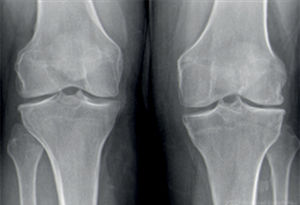

Lo que aportan las pruebas complementariasLas pruebas complementarias aportan información clave para el diagnóstico diferencial, aunque no siempre son necesarias de inicio. La radiografía simple suele ser la primera prueba y debe incluir proyecciones anteroposterior y lateral, preferiblemente en carga y de ambas rodillas. Si se pretende descartar fractura, es aceptable radiografiar solamente el lado afecto. La radiografía permite confirmar la presencia de artrosis de rodilla, mediante hallazgos como estrechamiento del espacio articular, esclerosis subcondral y osteofitos (fig. 3), además de ayudar a evaluar la severidad y guiar la decisión quirúrgica. No obstante, el diagnóstico de gonartrosis suele ser clínico en mayores de 45 años11, por lo que guías como la NICE (National Institute for Health and Care Excellence) recomiendan limitar la radiografía a las presentaciones atípicas, progresión rápida o sospecha de diagnósticos alternativos como enfermedad por depósito de pirofosfato cálcico o tumores. Ante sospecha de artritis por pirofosfato (pseudogota), es útil revisar radiografías previas de manos o sínfisis del pubis, que también son localizaciones típicas de condrocalcinosis (fig. 4).